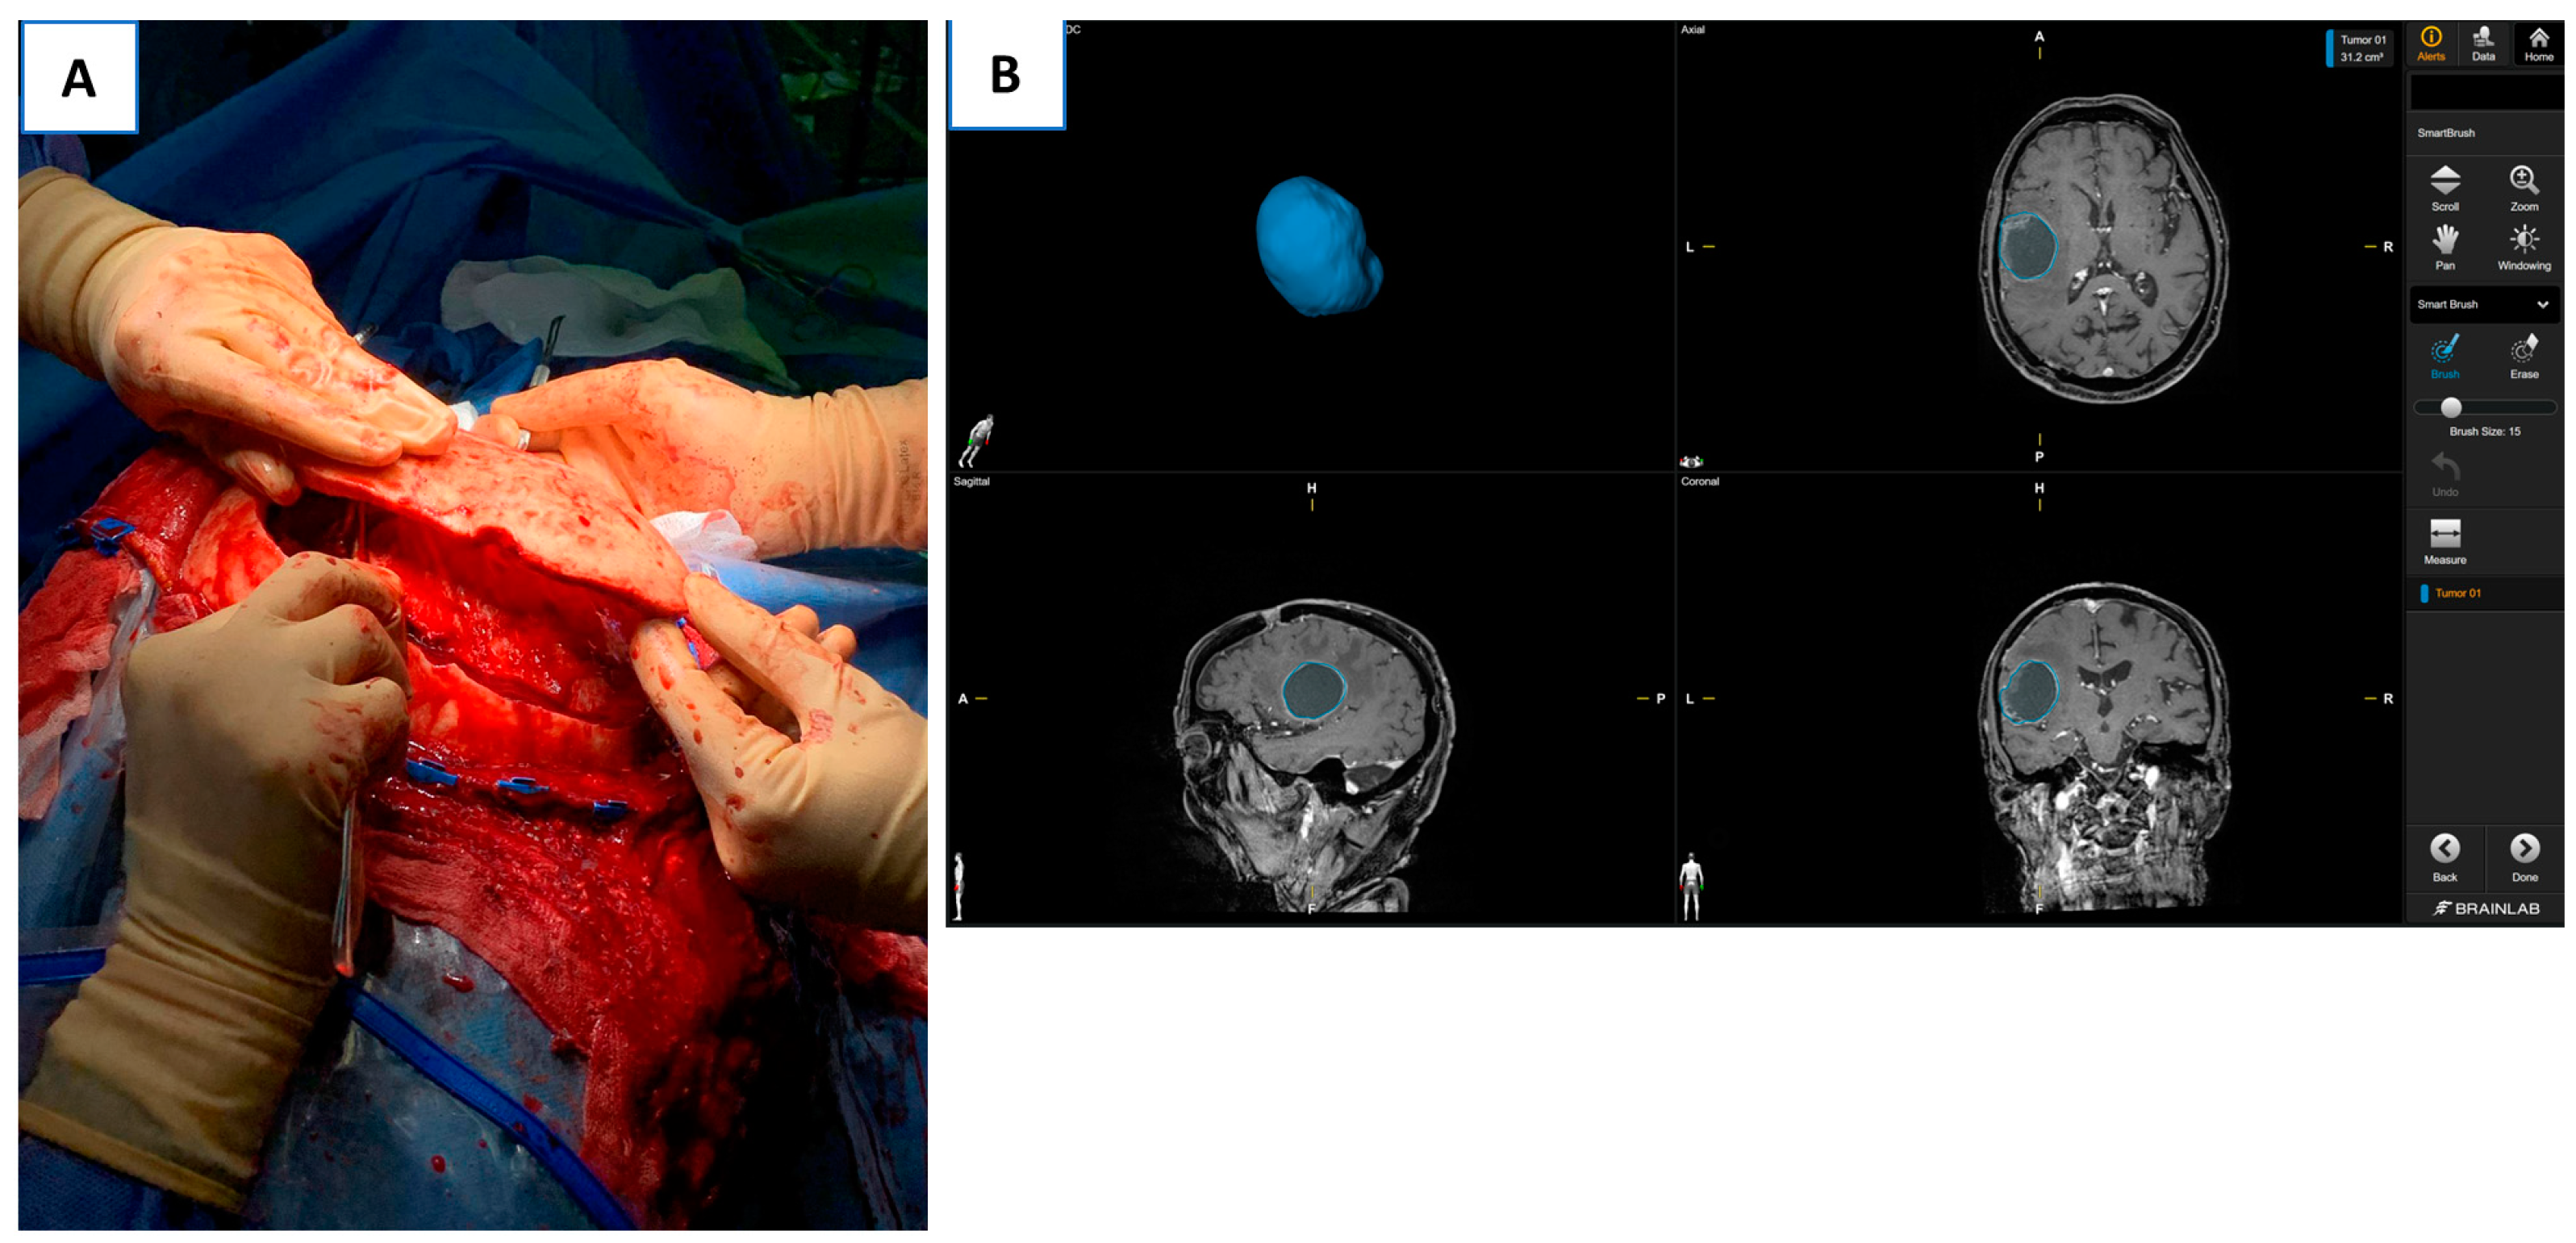

- Familiari, G.; Relucenti, M.; Heyn, R.; Baldini, R.; D’Andrea, G.; Familiari, P.; Bozzao, A.; Raco, A. The value of neurosurgical and intraoperative magnetic resonance imaging and diffusion tensor imaging tractography in Clinically integrated neuroanatomy modules: Across sectional study. Anat. Sci. Educ. 2013, 6, 294–306. [Google Scholar] [CrossRef]